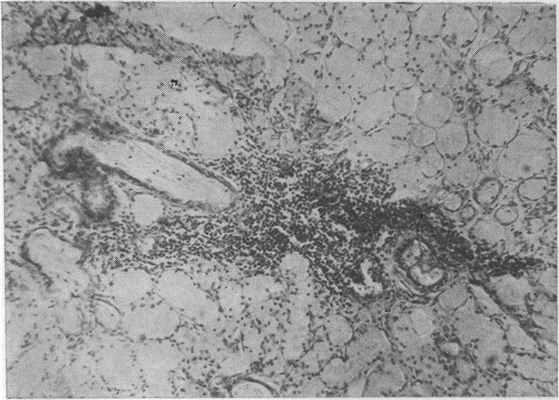

Рис. 38. Слизистые железы задней трети твердого неба женщины 53 лет, пользовавшейся протезом 6 лет. Круглоклеточная инфильтрация стромы. Окраска пикрофуксином. Х80 (Дуйшалнев К. Д.).

Изучение состояния надкостницы твердого неба и альвеолярных отростков беззубой верхней челюсти у лиц, пользовавшихся съемными протезами, показало следующее. При пользовании протезами до 3 лет надкостница альвеолярного отростка во всех возрастных группах утолщается вследствие очаговой пролиферации остеобластов. Последние резко увеличиваются в размере, иногда ориентируются параллельно поверхности кости, ядра их гиперхромны. В адвентициальном слое надкостницы коллагеновые волокна местами бледно окрашиваются, нередко разволокпяются. Аргирофильные волокна утолщаются. Эластические волокна нередко подвергаются фрагментации.

При увеличении сроков пользования протезами (более 3 лет) надкостница альвеолярного отростка и твердого неба заметно истончается (рис. 44), представляя собой плотную фиброзную ткань. Количество остеобластов

уменьшается. При большем сроке пользования протезами (более 8 лет) количество остеобластов в камбиальном слое уменьшается.

Необходимо подчеркнуть, что артериальные сосуды, залегающие в слизистой оболочке и надкостнице, часто имеют утолщенные гиалинизированные стенки. Подобные сведения о состоянии слизистой оболочки под пластиночными протезами сообщают F. Sin, W. Ger, Н. Мегап (1961), Т. Maj, Т. Zebro (1963), М. Dechaume с соавт. (1966).

Нервные элементы (мякотные и безмякотные волокна, а также концевые аппараты) подвергаются реактивным и деструктивным изменениям. Эти изменения чаще встречались и были более выражены в слизистой оболочке и надкостнице у пользовавшихся съемными протезами (рис. 45). Особый интерес представляет изучение реакции кости твердого неба и альвеолярного отростка беззубой верхней челюсти у лиц этой группы. Так, у людей в возрасте от 40 до 59 лет при пользовании съемными протезами до 3 лет прежде всего обращает на себя внимание отсутствие зоны остеоидной ткани в отличие от состояния кости твердого неба и альвеолярного отростка у не пользовавшихся съемными протезми. Края компактной кости выглядят слегка базофильными. В костных балках отмечаются признаки пониженного содержания солей кальция. Края их ровные. Но в отдельных случаях этой группы обращает также внимание отчетливая пролиферация остеокластов на границе кортикального слоя и периоста. Эти данные противоречат наблюдениям Б. Н. Бынина (1949) и Е. Pendleton (1940) о том, что съемные протезы способны стимулировать регенераторные способности кости.

Таким образом, морфологические исследования показали, что ткани протезного ложа беззубой верхней челюсти отвечают определенной реакцией на те необычные условия, в которых они оказываются под базисом пластиночного протеза. При пользовании протезами до 3 лет надкостница альвеолярного отростка утолщается. Но с увеличением сроков пользования протезами она, наоборот, истончается, превращаясь в плотный слой фиброзной ткани. Остеобласты камбиального слоя исчезают. В кости твердого неба и альвеолярного отростка после 3-летнего пользования протезами отмечается выраженная резорбция за счет остеокластов, дистрофические изменения и понижение регенераторной потенции кости. Костные балки значительно истончаются, обычная архитектоника нарушается. Костномозговые полости заметно расширяются. Костный мозг замещается жировой и фиброзной тканью. Определенные морфологические изменения претерпевают также сосуды и нервы слизистой оболочки, надкостницы и костного мозга.